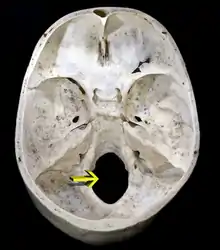

Gaura occipitală sau gaura occipitală mare (Foramen magnum) este un orificiu larg aflat pe porțiunea bazilară (Pars basilaris) a osului occipital. Are o formă ovală, alungită antero-posterior și este situată într-un plan aproape orizontal. Prin gaura occipitală canalul vertebral comunică cu cavitatea neurocraniului. Prin gaura occipitală trec bulbul rahidian (Medulla oblongata), arterele vertebrale (Arteria vertebralis), arterele spinale anterioare și posterioare (Arteria spinalis posterior și Arteria spinalis anterior), cei doi nervi accesori (Nervus accessorius). Meningele spinale se continuă la acest nivel cu meningele cerebrale. Ligamentul apical al dintelui axisului (Ligamentum apicis dentis) și membrana tectoria (Membrana tectoria) a articulației atlanto-axoidiane mediane trec prin gaura occipitală pentru a se fixa de porțiunea bazilară a osului occipital (Pars basilaris ossis occipitalis).